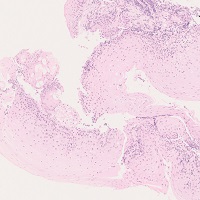

若年性ポリープ